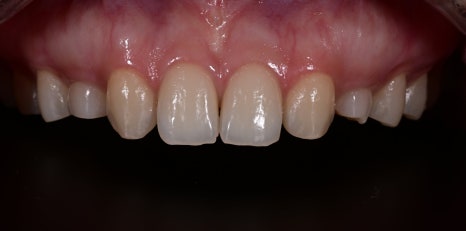

Why we proceeded with Obezero laminate veneers

This case

was treated with 16 Obezero laminate veneers.

The key to Obezero is naturalness

In this case as well,

- front teeth were brightened

- adjacent teeth were made to look natural

- overall balance was adjusted

By adjusting the color this way,

we completed “undetectable tooth shaping.”